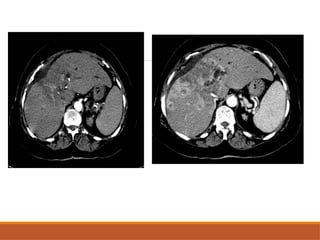

• #5 This is the axial cect image in arterial pjhase showing the well defined uniformly enhancing lesions – this is a case of hypervasculat metastasia from melanoma

On CT scan CECT- Discontinuous, nodular, peripheral enhancement starting at arterial phase & gradual central filling in. Retention of contrast in delayed phase. Enhancement must match blood pool in each phase(similar to aorta in arterial phase , portal vein in portal venous phase).

CECT - Discontinuous, nodular, peripheral

enhancement starting at arterial phase & gradual

central filling in.

Retention of contrast in delayed phase.

Enhancement must match blood pool in each

phase(similar to aorta in arterial phase , portal vein in

portal venous phase).